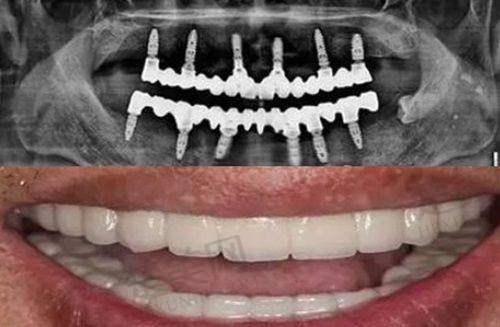

种植牙项目是深圳贝博口腔门诊部的特色之一。该门诊部引进了韩国进口种植牙和瑞士ITI亲水种植牙品牌。韩国进口种植牙性价比高,对于预算有限但又需要种植牙修复的患者来说是一个不错的选择。其种植体质量可靠,与人体组织的相容性较好,能够较快地与牙槽骨结合,修复牙齿的咀嚼功能。瑞士ITI亲水种植牙则具有更高的技术优势。它的亲水表面处理技术可以加速种植体与周围组织的愈合过程,缩短患者的修复时间。同时,其稳定性和成功几率都非常高,能够为患者提供更长久、更优质的牙齿修复成效。在种植牙过程中,门诊部还提供种植牙检查和即刻种植服务。种植牙检查可以全方面了解患者的口腔状况,为制定个性化的种植方案提供依据。即刻种植则可以在拔牙后立即植入种植体,减少患者的就诊次数和等待时间。